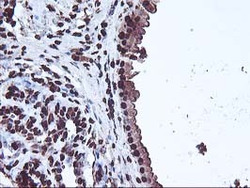

Immunohistochemistry

LS-C786085 IHC